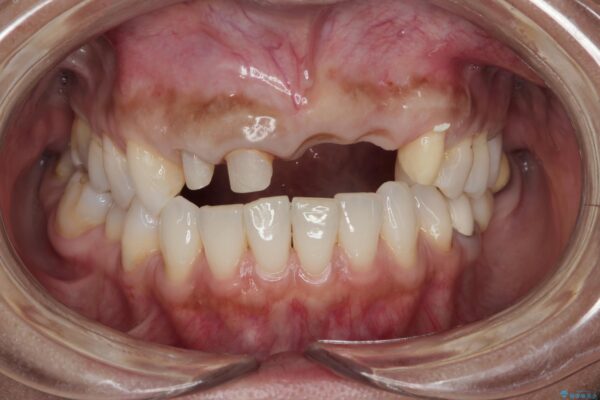

来院主訴

前歯がグラグラし、においもする、とのことで改善を求めて来院されました。

治療前

歯槽堤保存術を併用したブリッジ治療 治療前画像 歯槽堤保存術を併用したブリッジ治療 治療前画像 歯槽堤保存術を併用したブリッジ治療 治療前画像 歯槽堤保存術を併用したブリッジ治療 治療前画像 歯槽堤保存術を併用したブリッジ治療 治療前画像 歯槽堤保存術を併用したブリッジ治療 治療前画像 歯槽堤保存術を併用したブリッジ治療 治療前画像 歯槽堤保存術を併用したブリッジ治療 治療前画像 歯槽堤保存術を併用したブリッジ治療 治療前画像 歯槽堤保存術を併用したブリッジ治療 治療前画像